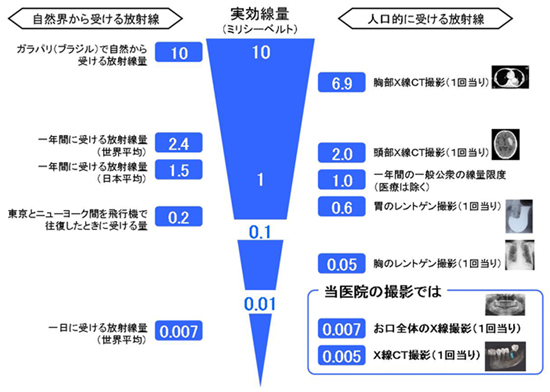

デジタルにより従来のフィルムを使用したレントゲン撮影に比べ、人体に受ける放射線の量を約1/4~1/10に抑える事が可能に、またCT(3D)機能により断層写真、立体的な撮影ができますので、インプラントのみならず、あらゆる歯科診療でより正確な診断と安全確実な診断が行えるようになりました。

CT撮影も実行照射時間の短縮により、患者様に必要以上のX線照射をすることなく診査・診断ができ、体にも安全です。